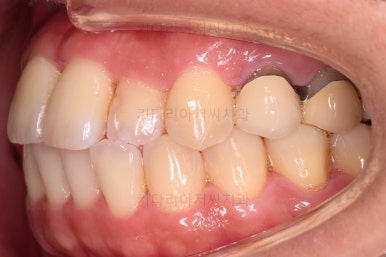

초진 시, 입안의 모습이에요.

결손부위가 눈에 띄고요.

결손부위가 양쪽에 있다보니 윗니 중간에 틈새가 벌어졌네요.

뒤쪽의 빈공간으로 치아들이 도미노처럼 쓰러져서 그렇습니다.

앞니의 약간의 틈새, 약간의 삐뚤어짐, 약간의 중앙선 틀어짐 등 심하진 않으나 약간씩의 문제점들이 있네요.